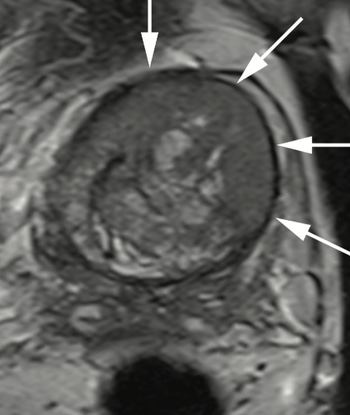

Dr. Judd W. Moul, MD, and colleagues present the case of a man, aged 73 years, with a prostate-specific antigen level of 110 ng/mL after 4 negative prostate biopsies and 4 negative prostate MRIs.